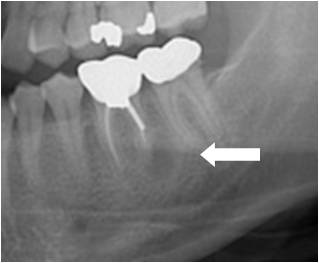

매복 사랑니(Impacted teeth)

증상

치아 통증

,

입 주변 부종

관련질환

치은염

진료과

치과